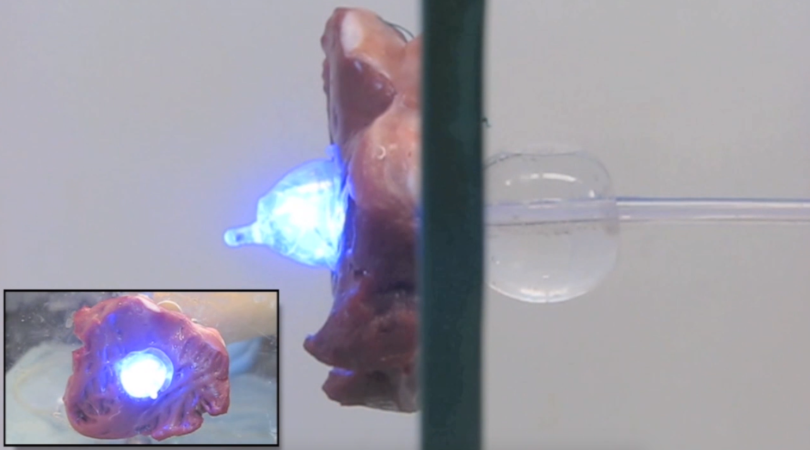

This was a try-before-you-buy treatment. Using X-ray fluoroscopy to guide a hollow needle, they insert electrodes into the space between bone and spinal cord, positioning this trial lead over specific nerves they think are causing the pain. The wires exit the body and connect to an external battery.

So I started my stim trial. For the next week, when I noticed the pain breaking through, I pushed a button. Instead of the pain, I felt the weird pulse of electrical current in my nerves.

Unlike my previous electrical experiences, this device actually drowned out my pain. It sent regular waves of electrical pulses through my nerves in a pattern called “tonic stimulation.” The most commonly used type of waveform technology, this feels like a continuous buzzing, or the tingles of a foot that’s fallen asleep. That’s not the most pleasant sensation, but I would trade suffering for vague buzziness any day.

But there was a final factor that elevated the Proclaim: It could apply a so-called burst waveform that I kept hearing the FDA would approve “any day now.” This pattern would allow me to avoid the buzzy, tingling sensations that had been the SCS norm. According to Amasha and my Abbott rep, burst stimulation better mimics the way your nerves naturally send and receive signals to make their current feel like nothing at all.

“Would you like to try the burst waveform? It just got approved by the FDA,” he said, adding that I’d be the first person in the Austin, Texas area to use this technology. He pulled out an iPad and started tapping away at his Clinician programing app. Within minutes, he had turned on my stim and handed me the sixth-generation iPod Touch that would, from that point forward, control the tech in my back. (I immediately dubbed mine the SpinePod.)

You know how you feel when you drink a shot of espresso, or your Advil kicks in, or you stand up straight and square your shoulders? Imagine that sensation of relief, but confined to your lower back. Turning on the burst stimulation in my device makes me feel like my foundations have shifted to a more secure footing. It feels like nothing—but a nothing that pushes the pain down.

Other painkillers distance me from the pain or cushion me from it, and that’s valuable. But it’s always lurking behind me. This isn’t like that at all. Unlike with the other treatments, there’s no promise of future agony. The SCS folds my pain up like complex origami, creasing and accordioning.

More than one year later, the SCS continues to banish much of my pain. The only side effect was that it also improved my mood—more than could be explained by just a lack of pain. The week after I began to use my spinal stimulator, my husband commented, “I don’t know if it’s the Burst or not, but you seem calmer than I’ve ever seen you.” According to a study assessing the Burst waveform, “It is specifically capable of influencing the affective/attentional components of pain.” In other words, the effect on my mood is real.